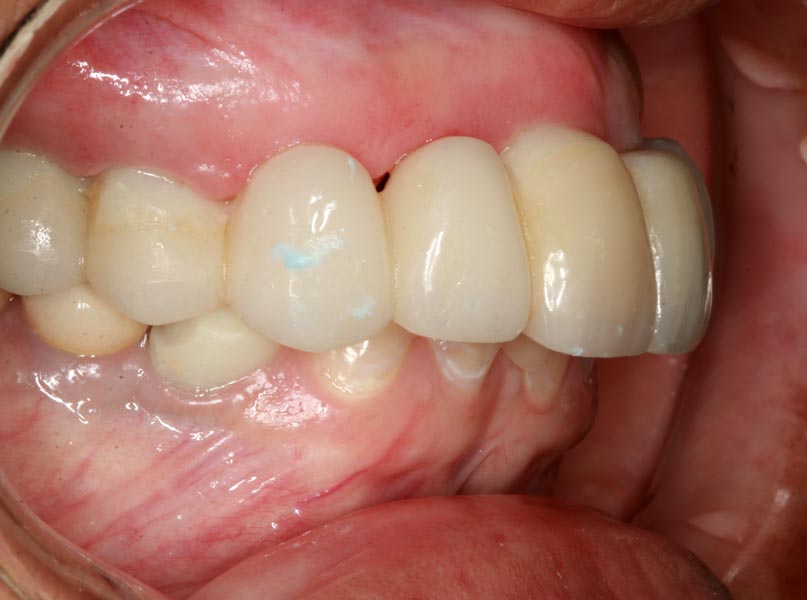

Smile GalleryImplant RestorationsFull Mouth Implant Restoration Full arch zirconia implant bridge (full smile) 1 of 37 Pre-op full smile Pre-op lips retracted Pre-op panoramic x-ray Extraction of strategic teeth Placement of implants Extraction of some remaining teeth after verification of adequate implant stability Occlusal view Post-op panoramic x-ray Immediately fabricated provisional restoration (tissue side view) Immediately fabricated provisional restoration (occlusal side view) Immediate provisional delivered on day of surgery Immediate provisional 2 weeks later Scalloped tissue developed from the provisional at 2 weeks Jig used for making a master impression Provisional in place (full smile) Provisional in place (lips retracted) Provisional in place (right side) Provisional in place (left side) Wax try-in (full smile) Wax try-in (right side full smile) Wax try-in (left side full smile) Wax try-in (full face, lips together) Wax try-in (full smile) Wax try-in (right side) Wax try-in (left side) Wax try-in (lips retracted) Full arch zirconia implant bridge on master cast (frontal view) Full arch zirconia implant bridge on master cast (occlusal view) Implant positions and soft tissue representation on master cast (occlusal view) Soft tissue representation on master cast (frontal view) Full arch zirconia implant bridge (tissue side view) Soft tissues on day of delivery (occlusal view) Soft tissues on day of delivery (frontal view) Full arch zirconia implant bridge delivered (lips retracted) Full arch zirconia implant bridge (lips retracted, close up) Post treatment panoramic x-ray Full arch zirconia implant bridge (full smile)